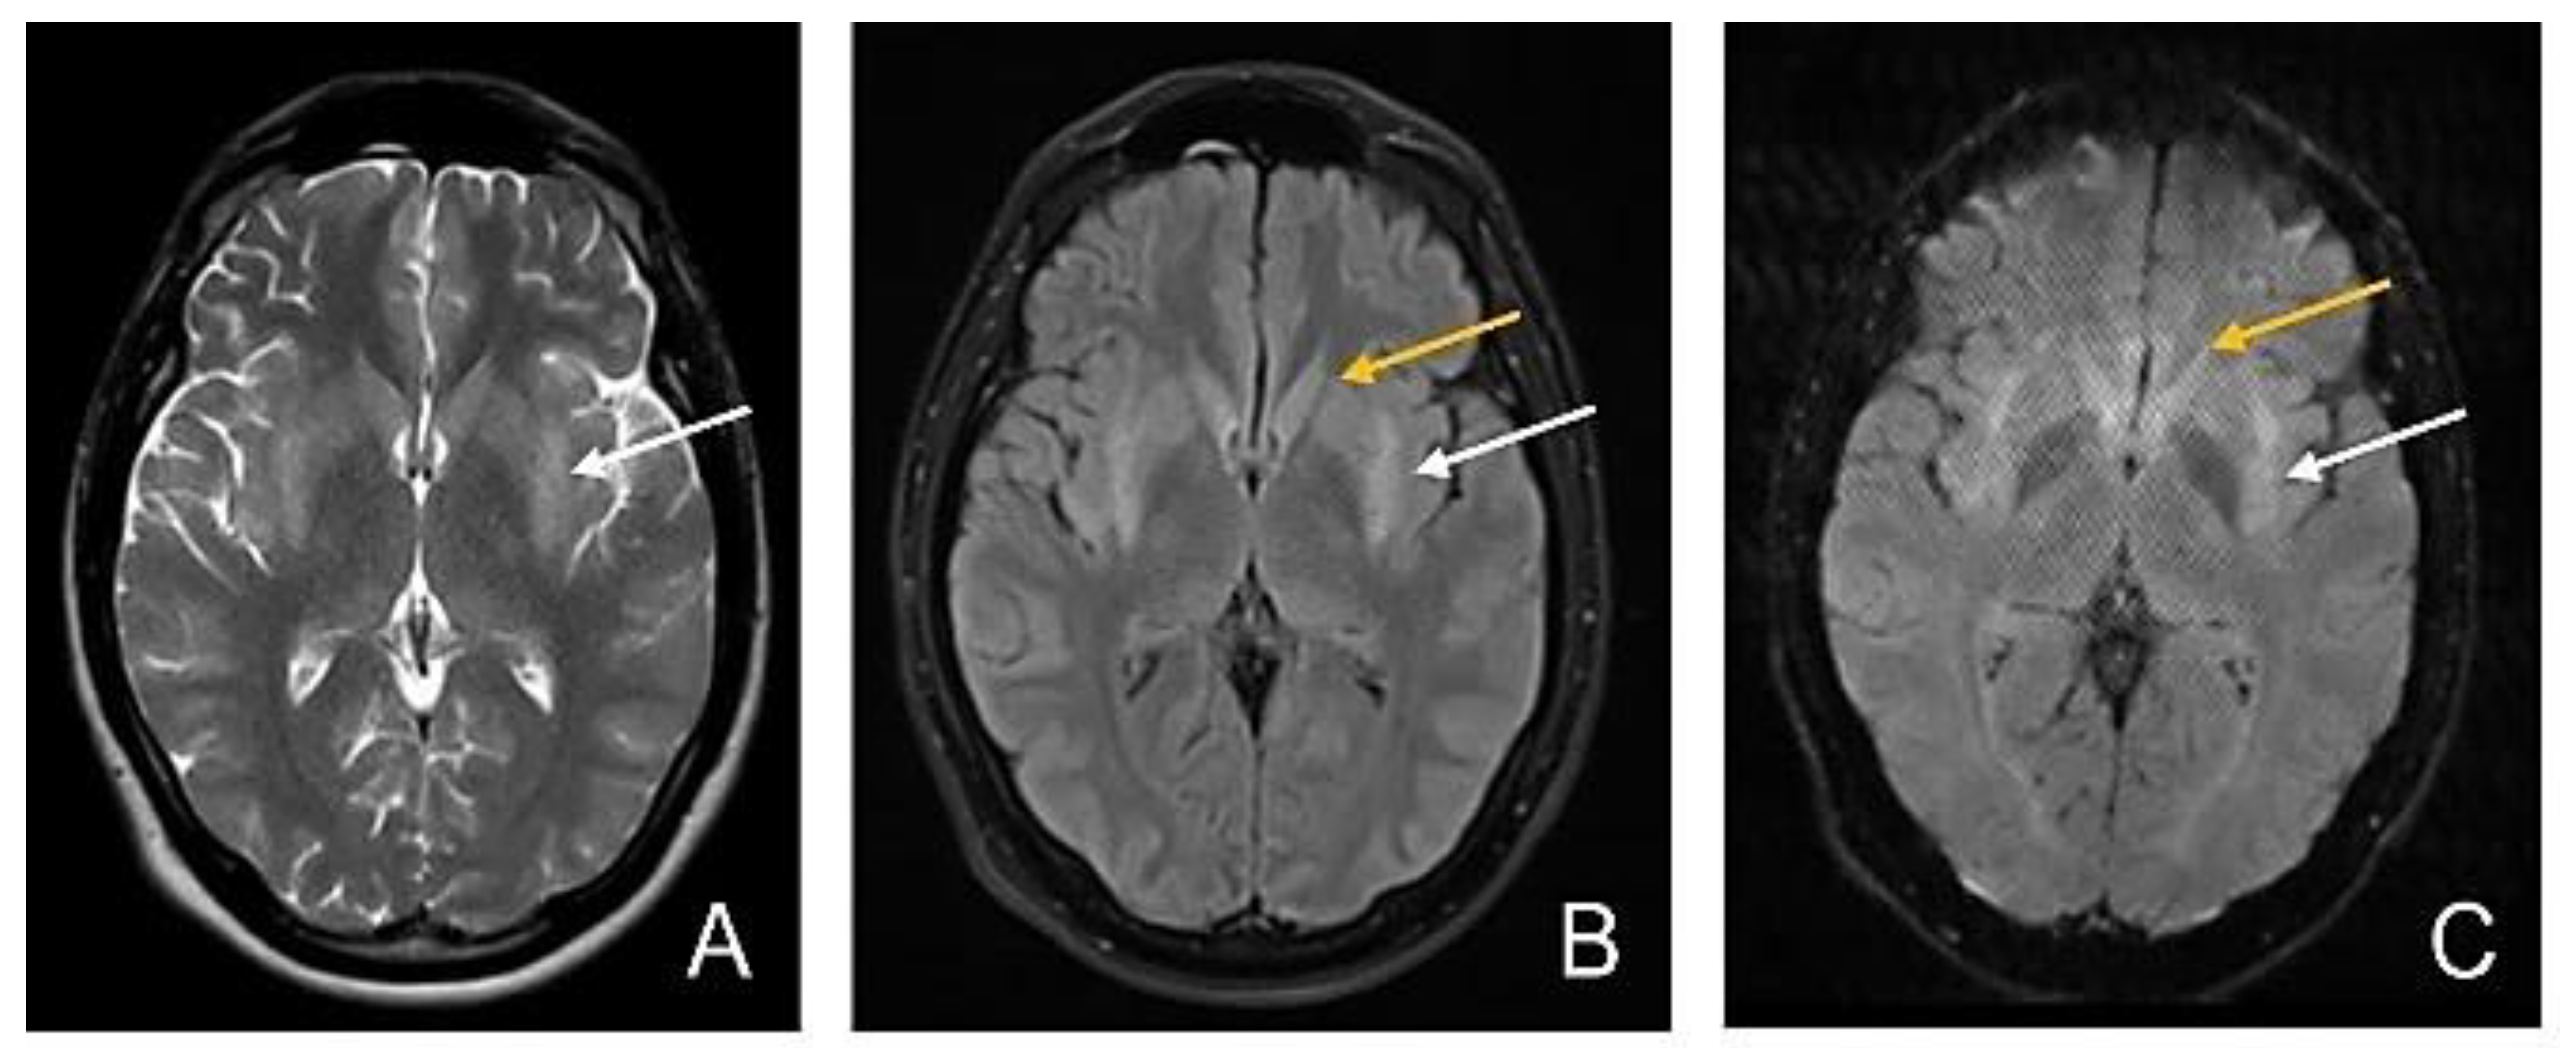

MRI Evolution of a Patient with Viral Tick-Borne Encephalitis and Polymorphic Seizures